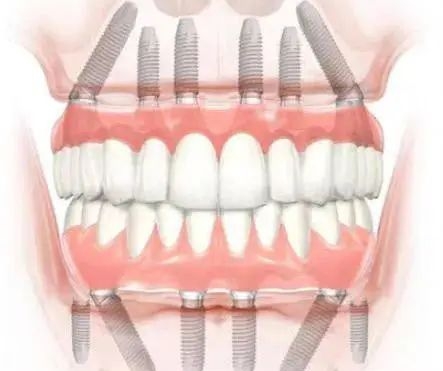

阮醫(yī)生參與研發(fā)了立得用種植技術(shù),這是中諾口腔數(shù)字化種植的核心技術(shù)體系。該技術(shù)通過計(jì)算機(jī)導(dǎo)板導(dǎo)航,實(shí)現(xiàn)了全口無牙頜即刻種植,即使牙槽骨重度萎縮的患者,也能通過內(nèi)外提升術(shù)和骨移植方案獲得良好療效。

如果你缺了半口或全口牙,數(shù)字化種植的優(yōu)勢(shì)較大。傳統(tǒng)種牙需要種很多顆,手術(shù)時(shí)間長、創(chuàng)傷大。而數(shù)字化種植可以用更少的種植體支撐整排假牙,比如All-on-4技術(shù),只需要種4顆種植體就能支撐半口假牙。